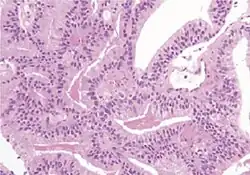

Acinar adenocarcinoma

These constitute 93% of prostate cancers.[2]

Microscopic characteristics

Specific but relatively rare

[notes 4]

• Collagenous micronodules[4]

• Glomerulations,[4] epithelial proliferations into one or more gland lumina, typically a cribriform tuft with a single attachment to the gland wall.[18]

• Perineural invasion.[4] It should be circumferential[18][notes 5]

• Angiolymphatic invasion[4]

• Extraprostatic extension [4]

Relatively common and highly specific

[4]

• Multiple nucleoli

• Eccentric nucleoli[4]

Less specific findings.

In uncertain cases, a diagnosis of malignancy can be discarded by immunohistochemical detection of basal cells.[4]